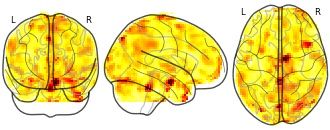

"name": "Multi_VBMsmaller_fMRIenhanced",

"description": "Multi-modal analysis in BPD. Brain regions exhibiting smaller gray matter and enhanced activation during emotion processing in BPD compared to healthy controls. Note: Results were thresholded at p<.0025. Note2: Results were updated (see Erratum for this publication).",